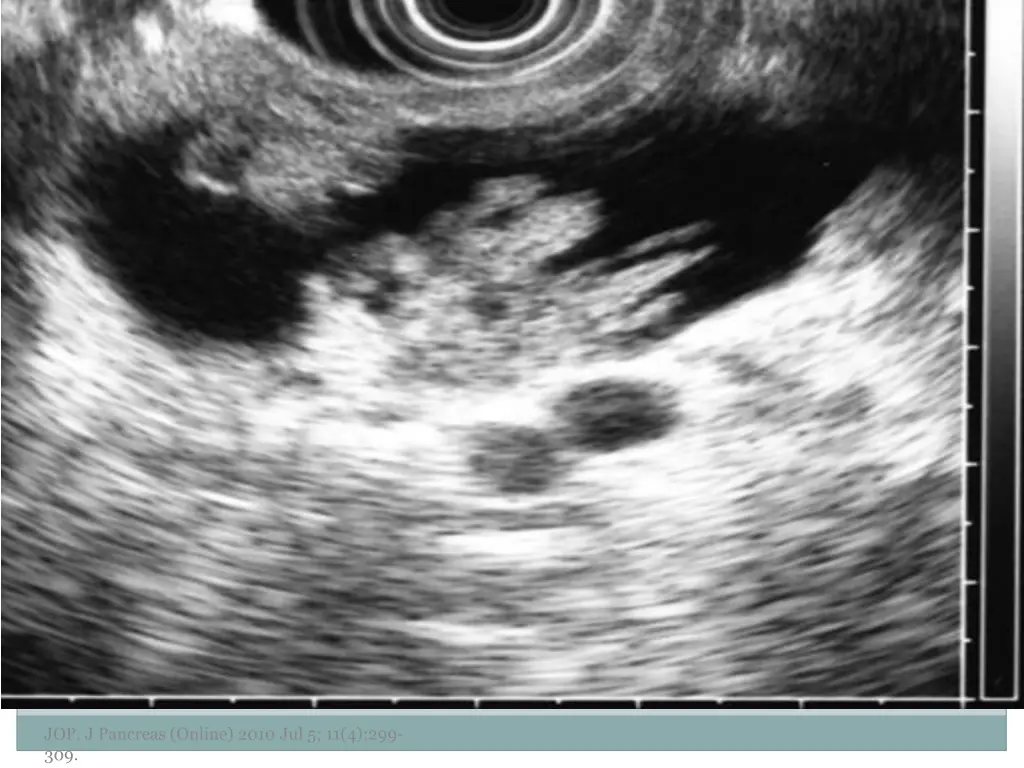

10. Examples of Morphology JOP. J Pancreas (Online) 2010 Jul 5; 11(4):299- 309.

11. JOP. J Pancreas (Online) 2010 Jul 5; 11(4):299- 309.

12. JOP. J Pancreas (Online) 2010 Jul 5; 11(4):299- 309.